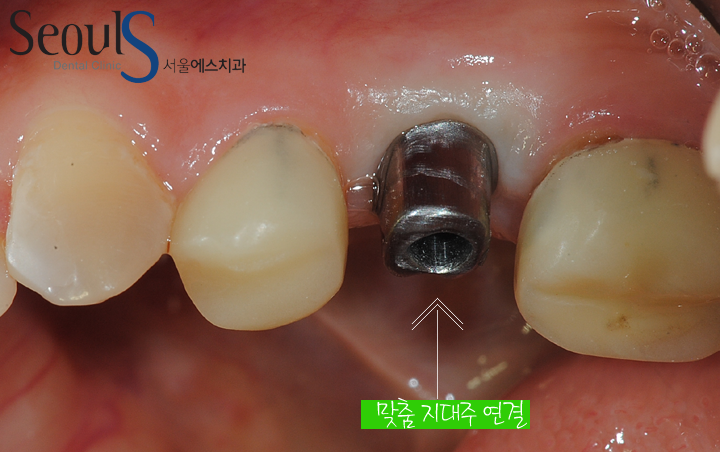

맞춤 지대주를 연결한 모습입니다

맞춤 지대주 사용 (Abutment)

기존 지대주 (Abutment)는 공산품처럼 천편일률적으로 생산됩니다

환자분의 구강상태는 모두 다른데…말이죠

서울에스치과는 광진구 최초 캐드캠(CAD/CAM) 시스템 장비를 보유하여

환자의 구강상태에 적합한 맞춤형 지대주(Abutment)를 생산이 아닌 제작을 합니다

기성 지대주(Abutment) VS 서울에스치과 지대주 (Abutment)

-광진구 최초 3D CAD/CAM 기술을 바탕으로 환자의 잇몸 상태를 고려하여 가장 좋은 모양으로 맞춤 제작합니다.

-최종 보철물을 치과의사가 설계하고 전문 기공사가 제작함으로 안전성 및 심미적 완성도가 높습니다

-의료용 Titanium Alloy 와 zircona 소재를 사용하여 인체에 알레르기 반응 및 임플란트 주위 염을 최소화합니다